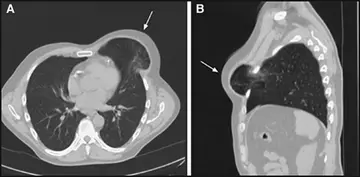

فتق ریه بعد‌از عمل

یک سال پس ازجراحی بای پس سرخ‌رگ کرونر به صورت مستقیم و با حداقل تهاجم یک مرد 67‌ ساله به‌علت وجود دفورمیته با حدود مشخص مراجعه کرد که از بالای فضای بین‌دنده‌یی سوم چپ بیرون‌زده وهمی‌توراکس قدامی چپ ایجاد شده بود.